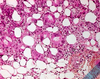

Tinea